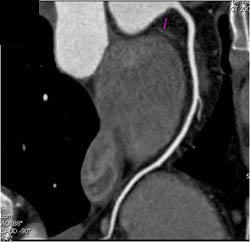

Diagnosis

Normal LAD